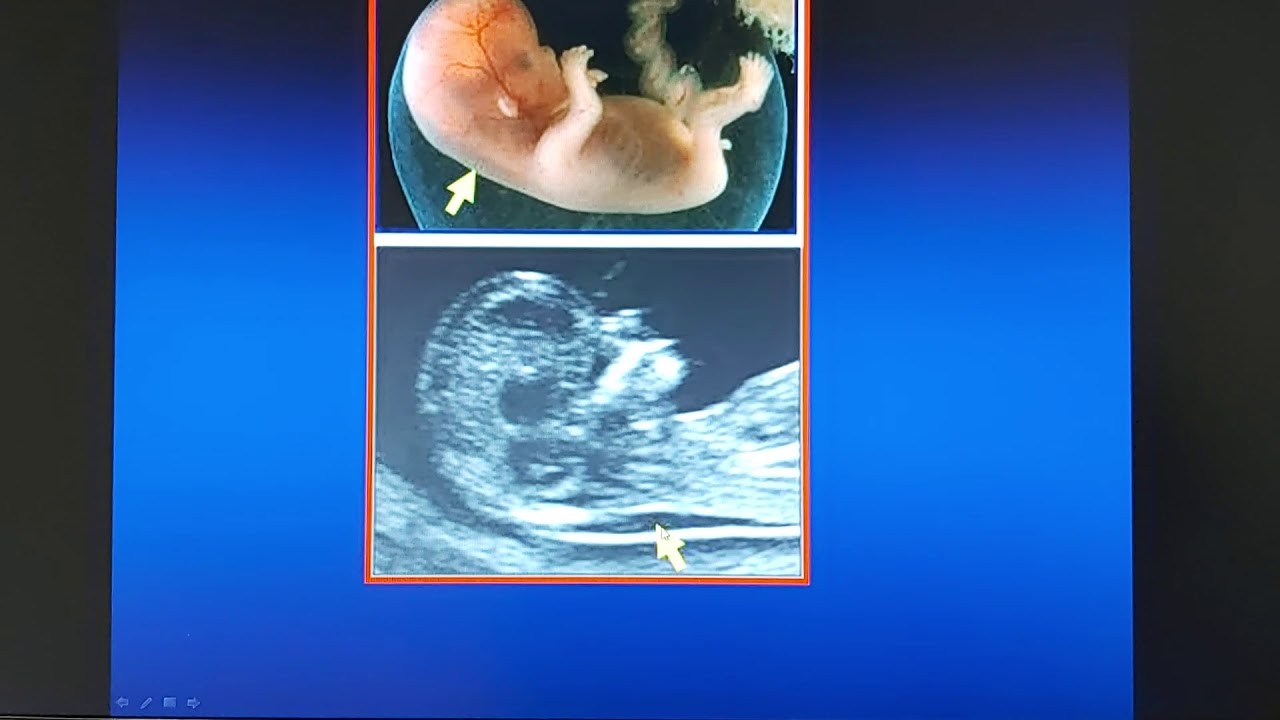

L'ecografia è un esame utilizzato nel primo trimestre di gravidanza per la datazione della gravidanza e per la misurazione di un parametro importante che è la translucenza nucale .Nel secondo trimestre l'ecografia si utilizza per studiare l'anatomia fetale e il suo accrescimento.

Purtroppo la sensibilità dell'esame ecografico nel visualizzare le malformazioni non supera per alcuni organi il 50%.